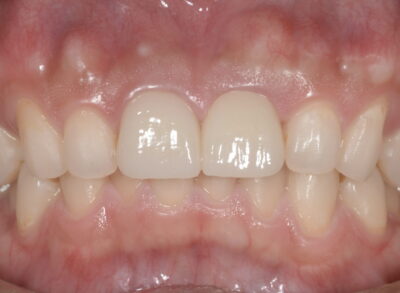

HAMADA DENTAL CLINIC 当院はチーム医療で世界基準の先端治療を提供する初台の歯医者です。他院で「治療不可」「抜歯」「抜髄」と診断された難症例の患者様を数多く受け入れています。

重度の虫歯や歯周病はもちろん、歯並び・歯の形や色など見た目の悩みにも対応できる歯医者です。多様な先端治療であらゆるお悩み・症状に対応します。

虫歯の最終形態、難治性根尖性歯周炎から歯を救う「歯根端切除術」や、グラグラの重度歯周病を改善する「歯周組織再生治療」など、世界基準の先進医療を日々実践しています。